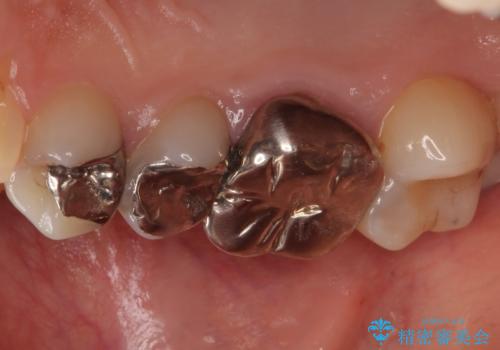

- 笑ったときに見てしまう上顎奥歯の銀歯を気にして来院された患者様です。

折角セラミッククラウンを装着するので、根管治療を行った後に補綴治療を行うこととしました。

他にも目立つ銀歯がありましたが、最も気にしている2本を優先して行うこととしました。